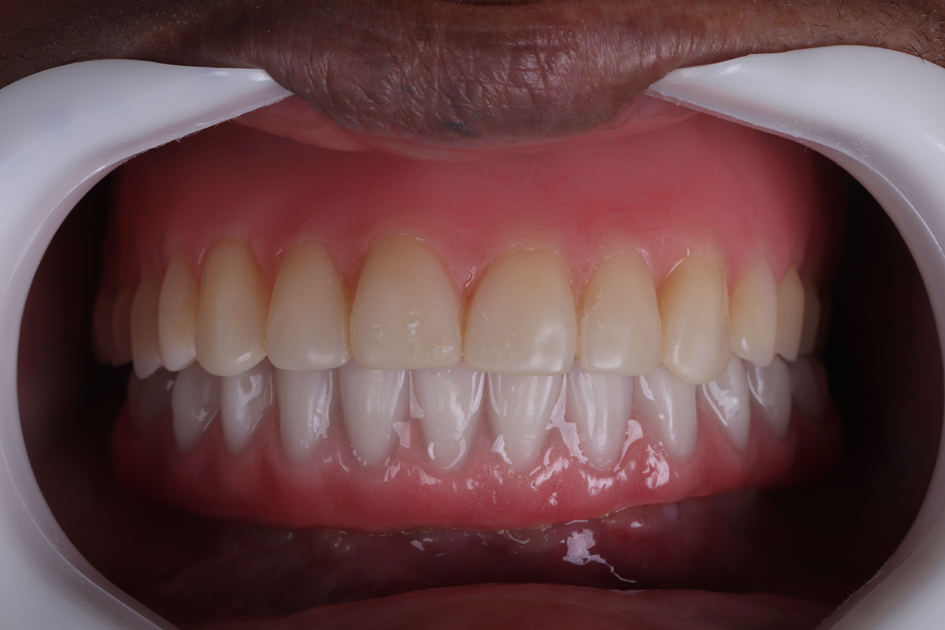

Figura 26 – Foto da prótese protocolo inferior definitiva instalada em boca.

Figura 27 – Foto da prótese protocolo inferior definitiva instalada em boca.

Figura 28 – Foto da prótese protocolo inferior definitiva instalada em boca.